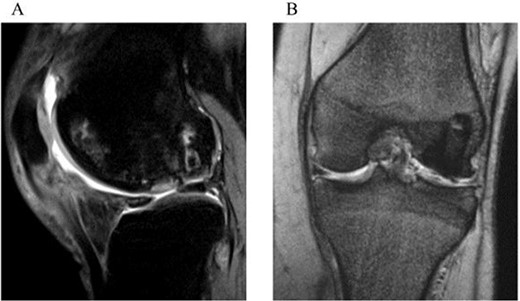

One year after surgery, the visual analog scale (VAS) score had improved to 0, and the ROM for extension and flexion were recovered to 0° and 140°, respectively. At 2 years, the Knee Injury and Osteoarthritis Outcome Score improved to 494, the VAS score remained at 0, and ROM of extension and flexion were fully recovered to 0°–145°. The follow-up MRI exhibited healing and consolidation of the osteochondral graft with the smooth articular surface attained at the grafted area (Fig. 4a and b).

Two-year postoperative MRI. A sagittal fat saturation T2-weighted image (a) and a coronal T2-weighted image (b) show smooth articular surface in the grafted area and consolidation of the transplanted bone plugs.